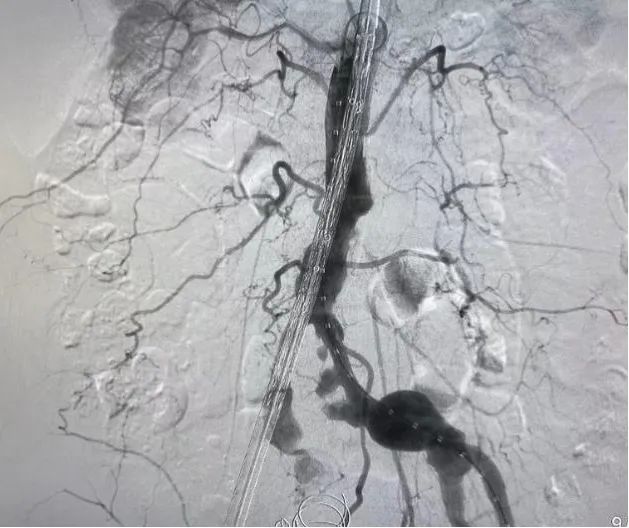

术后DSA复查造影 右侧髂内动脉瘤及左侧髂总动脉瘤未再显影-拆弹成功